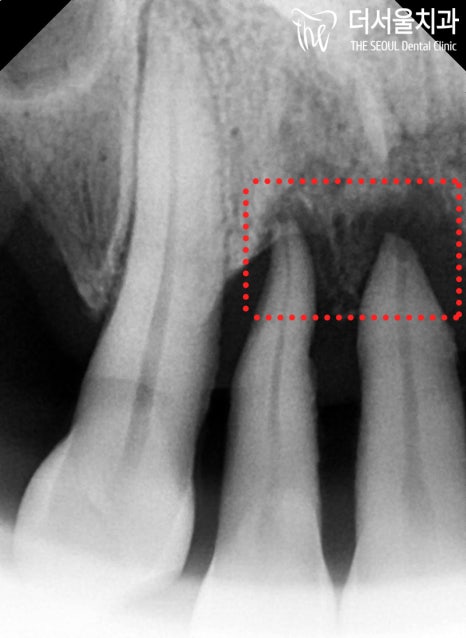

전반적으로 상태가 너무 안 좋습니다.

잇몸이 많이 내려앉아 있으면서

뿌리가 거의 다 드러나 있었죠.

언제 떨어지더라도 이상하지 않을 정돕니다.

교합면을 보면 더 심각합니다.

양 측면을 보더라도

좋지 않다는 것을 볼 수 있습니다.

우선 잇몸뼈가 얼마나 남아있는지

정확한 진단이 필요했기에

파노라마 엑스레이를 촬영하여 확인해봤는데요.

2. 뼈 상태 체크

치아가 있는 곳을 제외하고는

잇몸뼈는 거의 없는 상태입니다.

그리고 앞니 역시 마찬가지로

뿌리 끝에만 걸치고 있는 상황이었습니다.